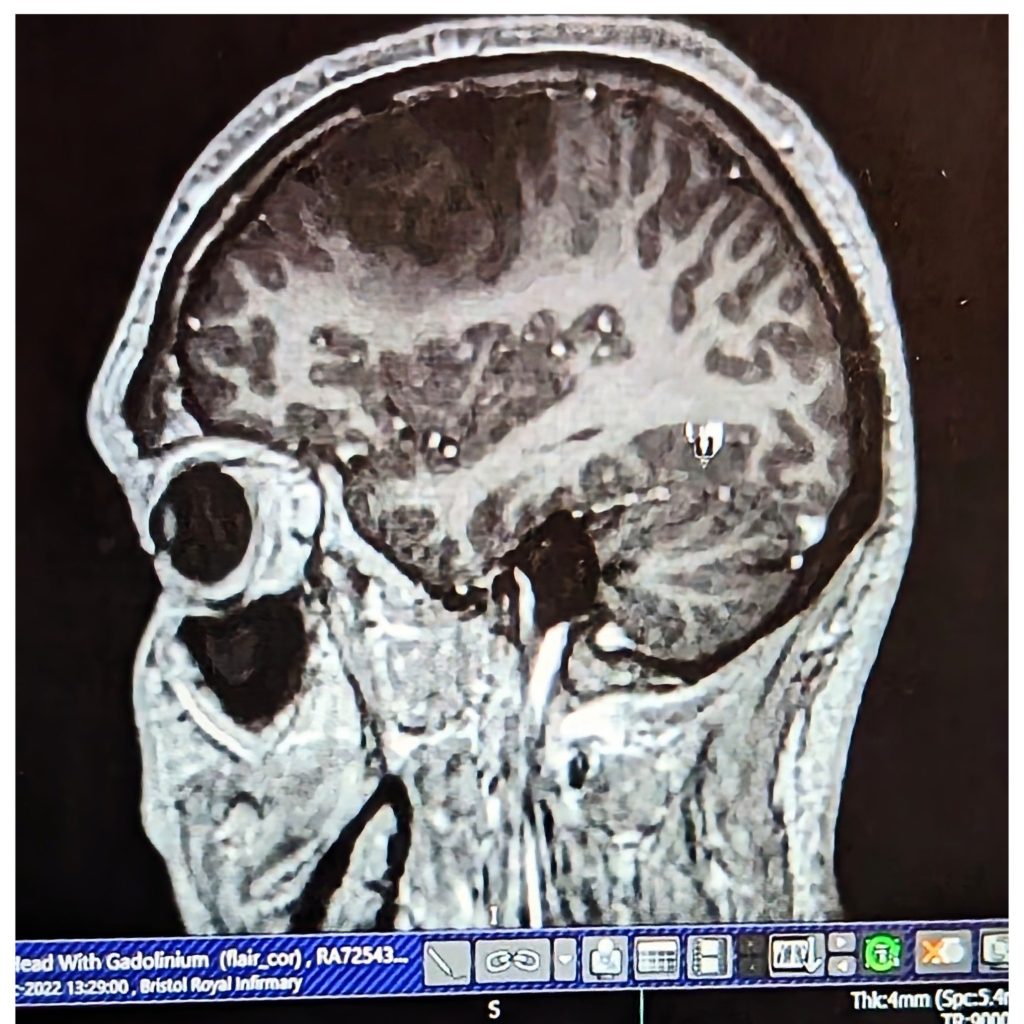

The second order of business to come was the MRI with added contrast with a dye known as Gadolinium. This took about 45 minutes and was honestly not too bad with some happy thoughts and the pro-tip of double ear protection (Both inner and outer.) If you’re lucky enough to have long one like me!

The most likely diagnosis was a suspected low-grade glioma (LGG). Although they can never be fully sure until they send off for further tests. Located on the left frontal lobe of the brain, it was close to speech and language sections as well fine motor control of the right hand side. It was suspected to be slow growing as indicated areas of low attenuation, which I took as a positive sign and had likely been growing for years. They were cautious to avoid being drawn on the extract grade, but simply put, most if not all low-grade tumours progress to high-grade ones eventually, so aggressive intervention involving surgery was deemed to be very likely.

The Dr’s I had managed to speak to so far were from various random specialities. It had seemed like every one except neurology. In saying this they were very helpful and took me though me scans which I found intensely interesting and horrifying in equal parts. What was immediately clear to me that this was no small mass. It was difficult to say the exact dimensions but my little ‘friend’ had grown to quite a size! I made a mental note to give my tumour a name eventually!

Here’s an image that I did manage to get at this early stage. The tumor is the dark blob that can be seen to the frontal section of the brain.